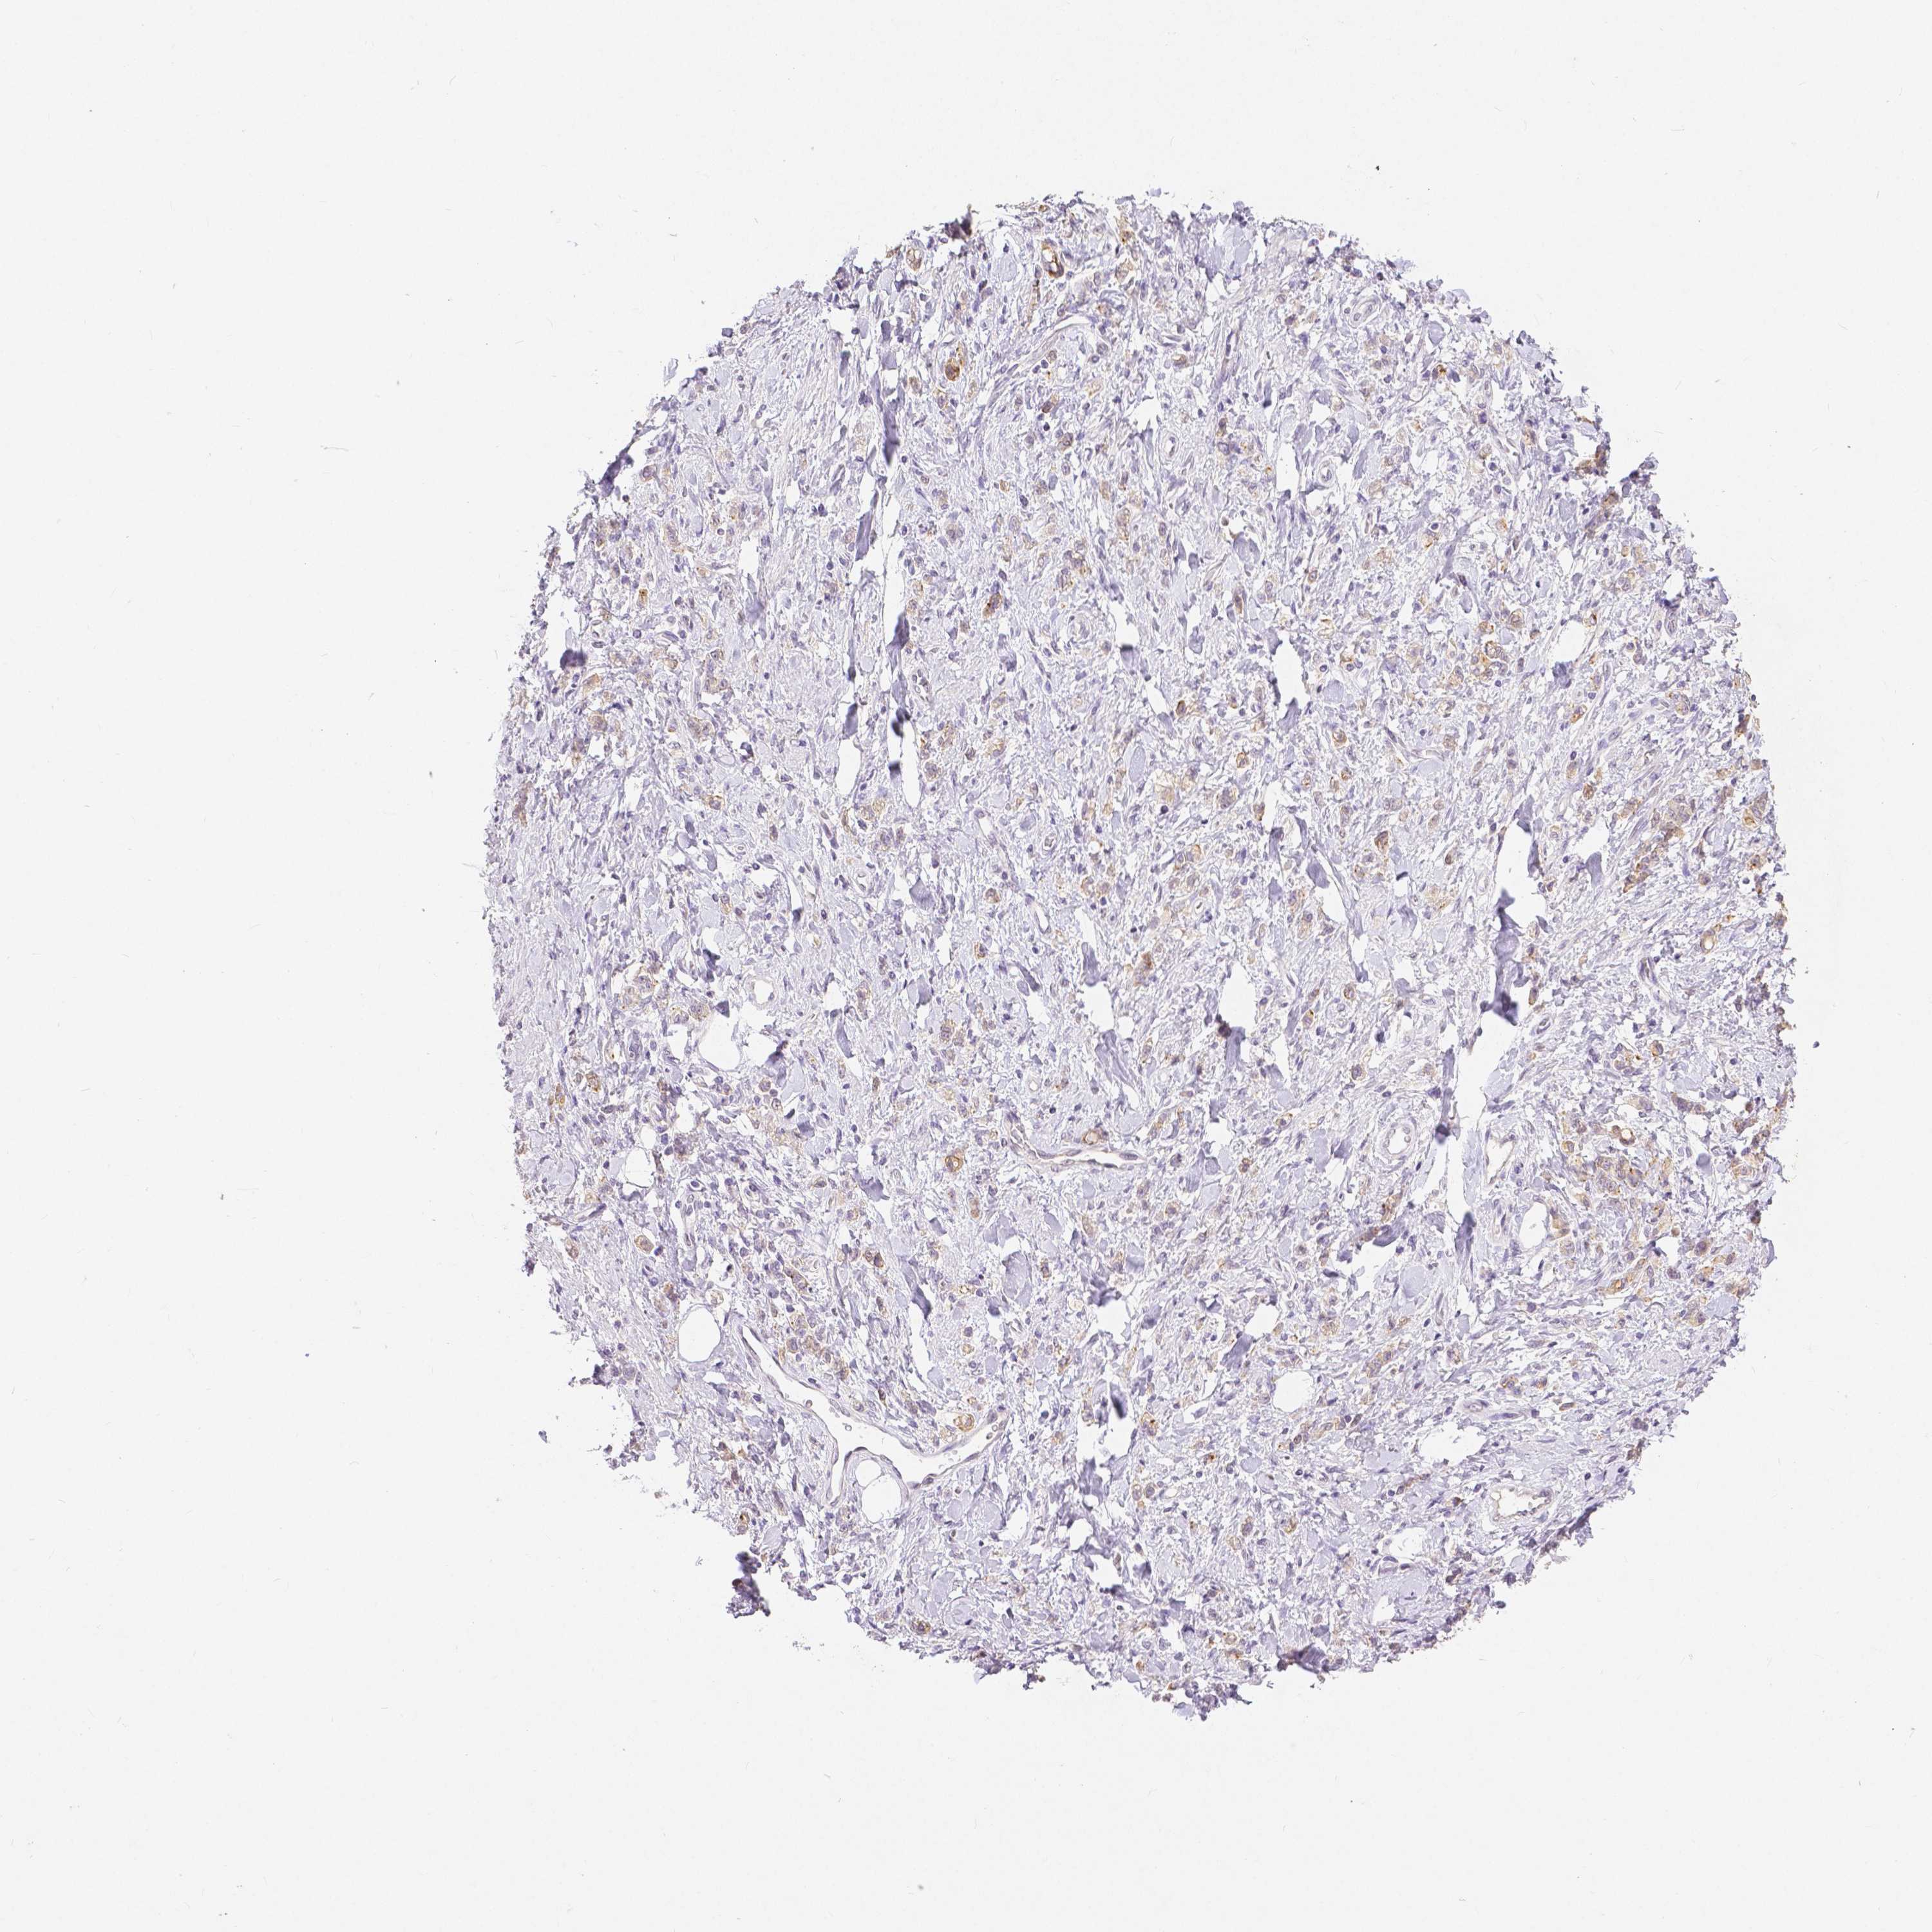

STOMACH CANCER - Protein expressioni

A mouse-over function shows sample information and annotation data. Click on an image to view it in a full screen mode. Samples can be filtered based on level of antibody staining by selecting one or several of the following categories: high, medium, low and not detected. The assay and annotation is described here.

Note that samples used for immunohistochemistry by the Human Protein Atlas do not correspond to samples in the TCGA dataset.

Antibody stainingi

Antibody staining in the annotated cell types in the current human tissue is reported as not detected, low, medium, or high, based on conventional immunohistochemistry profiling in selected tissues. This score is based on the combination of the staining intensity and fraction of stained cells.

Each image is clickable and will lead to virtual microscopy that enables deeper exploration of all samples and also displays staining intensity scores, fraction scores and subcellular localization as well as patient and tissue information for each sample.

HPA005933

CAB013075

CAB068212

CAB068213

CAB068214

Adenocarcinoma, NOS

Adenocarcinoma, High grade